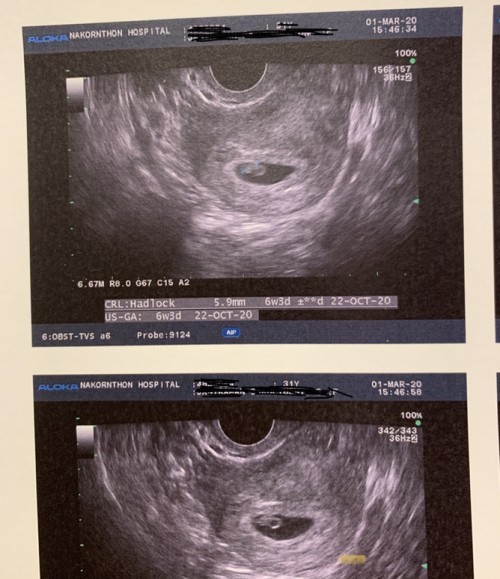

ตั้งท้องได้6สัปดาห์อัลตร้าซาวด์วันนี้หมอบอกว่าเห็นแต่ถุงตั้งครรภ์ยังไม่เห็นน้องค่ะ นัดอัลตร้าซาวด์ใหม่เดือนหน้า

บ้านนี้ซาวด์ผ่านช่องคลอดคะถึงเหน

6w3d เห็นตัวและหัวใจ ซาวด์ทางช่องคลอดค่ะ